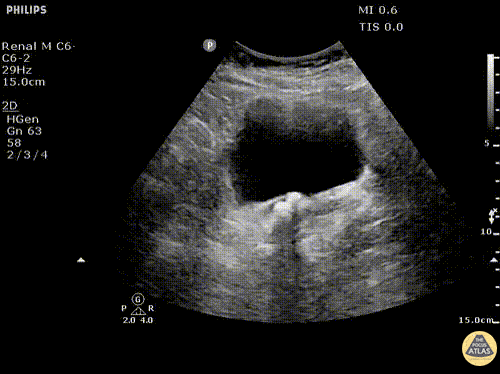

Renal/GU - Ureteral Stones at Ureterovesical Junction

Multiple ureteral stones visualized at UVJ with notable ureteral peristalsis. Image courtesy of Robert Jones DO, FACEP @RJonesSonoEM Director, Emergency Ultrasound; MetroHealth Medical Center; Professor, Case Western Reserve Medical School, Cleveland, OH View his original post here